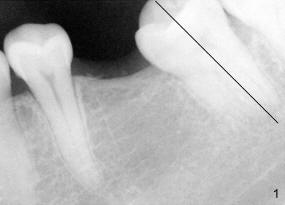

The tooth #19 has been lost for 8 years with tilting of #18 (black line in Fig.1). A 6x8 mm Bicon implant (3 mm post) was placed as distal as possible (I in Fig.2). Three months later, the implant was uncovered with evidence of osteointegration (arrowheads in Fig.3). A 4x6.5 mm 0 degree non-shouldered abutment with 3 mm post (A) was inserted into the implant well. The flat surface of the abutment needed to face distal in order to seat the abutment without interference. The implant/abutment complex was used as an anchorage to upright #18. The tooth #17 was extracted prior to orthodontic treatment (compare Fig.5,6 vs. 1-3). A bracket was bonded to Jet temporary crown of #19 and open coil spring was placed between #18 and 19. In the first two months, distalization of #18 is limited (between black and white lines in Fig.4), partially due to the fact that the bracket of #19 was debonded quite easily. A premolar band (B in Fig.5) was cemented to the temporary crown of #19. In another two months, the tooth #18 was pushed to desired position (arrowhead) under the tension of open coil spring (*). The mesial crest height of #18 was increased during uprighting (arrow, as compared to Fig.1-3). A new temporary crown was fabricated to fit the enlarged space of #19 with cementation of a molar band. The next problem is that the new molar temporary crown was easily dislodged from the 4x6.5 mm abutment even with a permanent cement. A larger abutment (5x6.5 mm) was used (Fig.6), with relining the temporary crown. The upper end of the larger abutment has sharp edge (Fig.8: white arrowhead, as compared to rounded edge of the smaller abutment (Fig.7). This may also contribute to better retention. In another 3 months, the temporary crown was dislodged again. An even larger abutment (6.5x6.5 mm with two flat surfaces (blue arrowheads in Fig.9) was adopted.